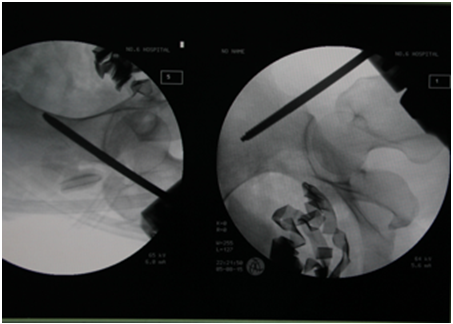

術(shù)中的透視可以看到患者盆腔內(nèi)留了大量紗布(圖片來源:芮碧宇/攝)

有這樣一個案例,2015年8月的一個傍晚,黃女士突遇車禍,被土方車碾壓,生命垂危。下級醫(yī)院簡單處理后,直接轉(zhuǎn)運(yùn)到上海市第六人民醫(yī)院急診科,到達(dá)急診科后,黃女士的血壓只有60/30mmHg,心率高達(dá)每分鐘165次,處于嚴(yán)重失血性休克的狀態(tài),CT檢查顯示骨盆嚴(yán)重骨折,盆腔內(nèi)大量出血,再不止血黃女士就會有生命危險。生活中我們?nèi)绻簧魇軅鲅,最快的止血方法就是壓迫傷處,對于黃女士這么嚴(yán)重的內(nèi)出血,醫(yī)生能做什么?答案也是壓迫。用什么?就是用紗布。此時,醫(yī)生迅速為黃女士安排了手術(shù),手術(shù)就做了兩件事,一是臨時固定骨盆,二是打開盆腔填塞紗布,這是最迅速、最有效的處理腹腔、盆腔和子宮大量出血的手段。如果止血有效,通常在48-72小時后從患者體內(nèi)取出這些紗布,當(dāng)然填入的紗布是嚴(yán)格計數(shù)的。在取出時,紗布將被嚴(yán)格清點(diǎn)并透視以確認(rèn)沒有殘留。對于黃女士來說,經(jīng)過填塞手術(shù),內(nèi)出血得到了控制,醫(yī)生將她從死亡邊緣救了回來,換句話說,是她肚子里的紗布救了她。經(jīng)過治療后,黃女士康復(fù)出院。